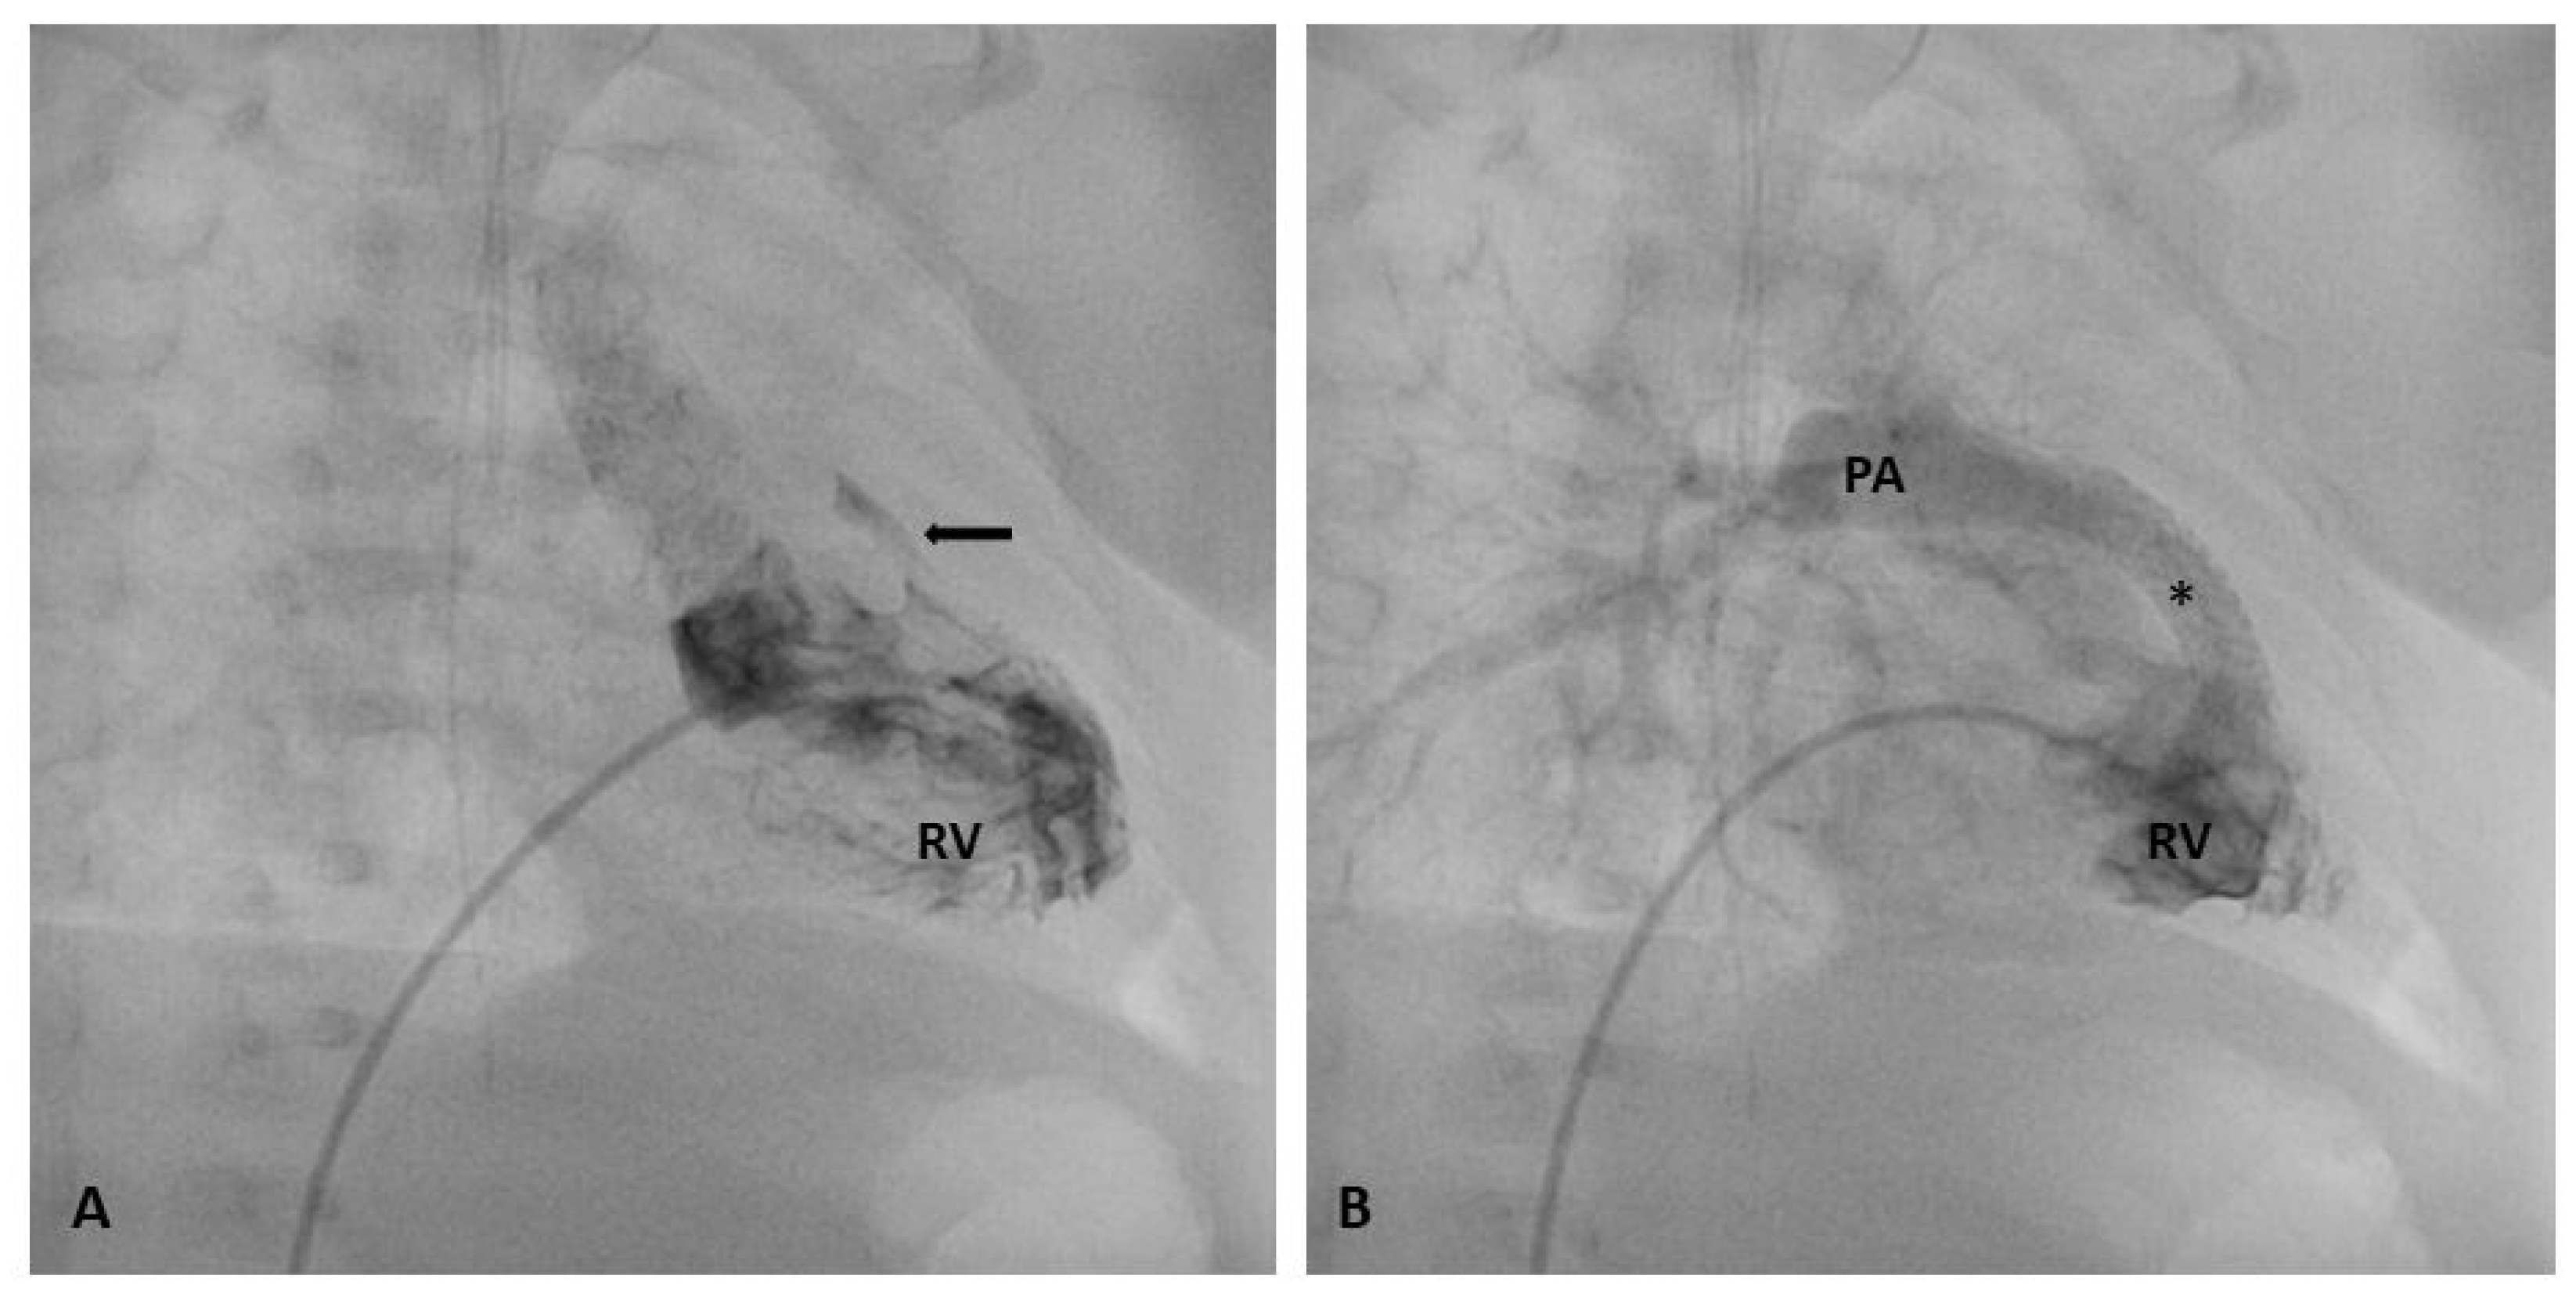

1.5. Procedural Technique: RVOT Stenting